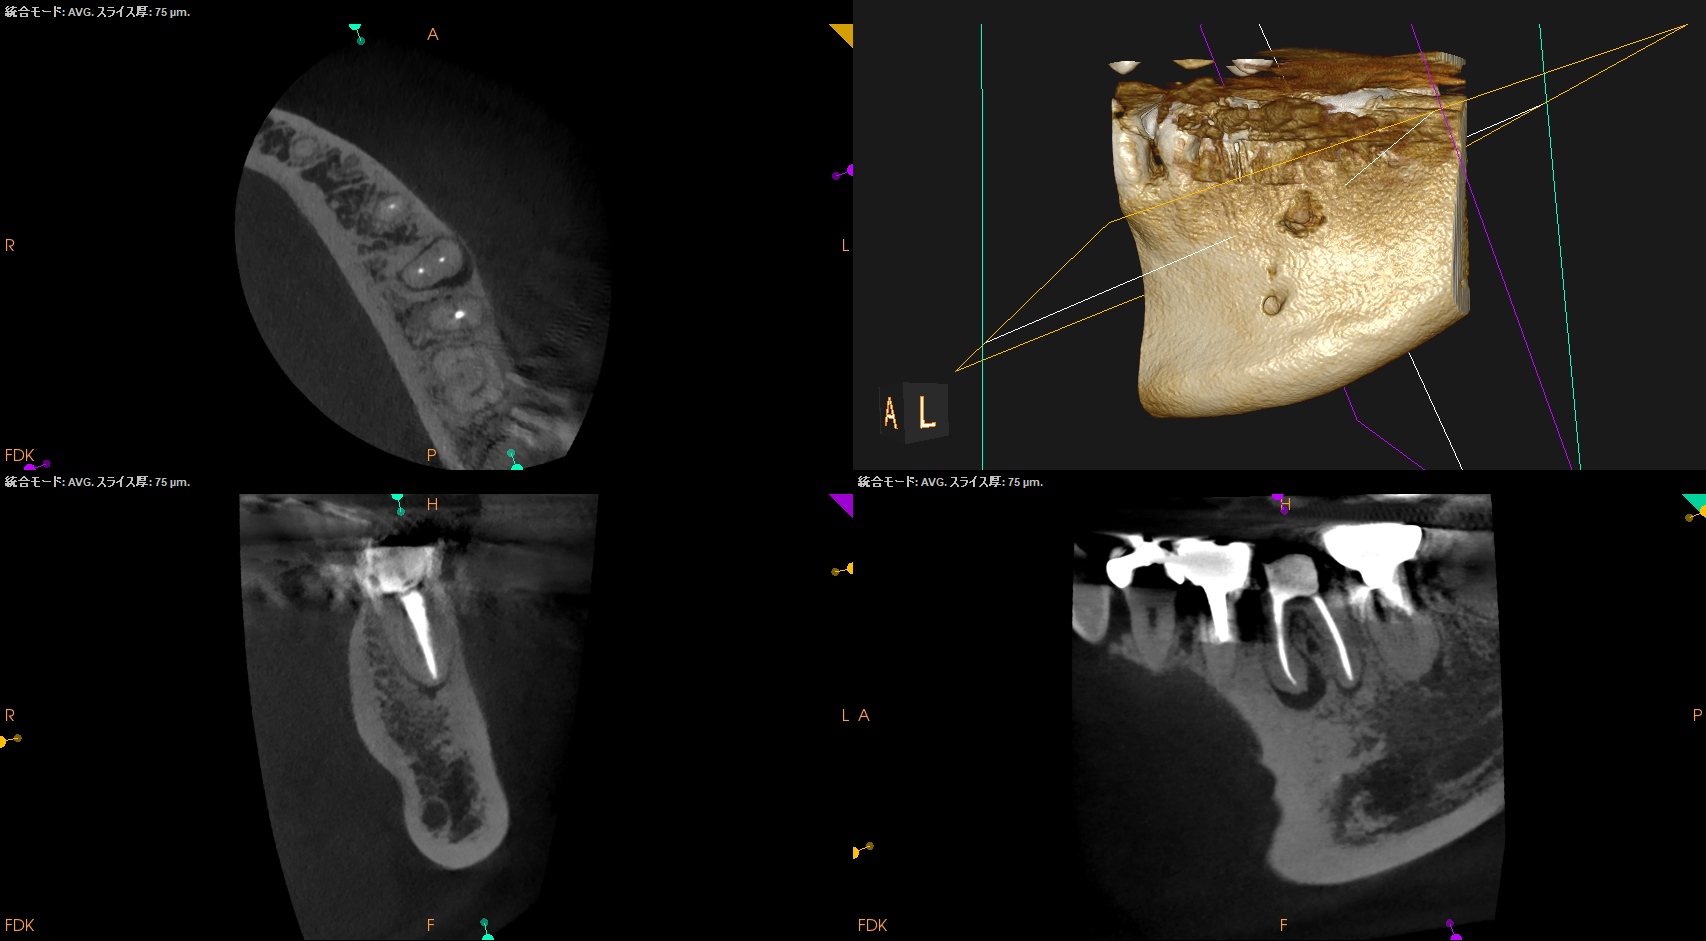

Pre-op CBCT(2025.1.10)

MB

ML

D

根尖病変があるのは近心根のみであるので近心根のみ再根管形成することにした。

MBもMLも穿通させる必要があることがCBCTを見える絵にしていけばわかる。

が、世の中のほとんどの人はこの作業ができない。

ほとんどの人はCBCTを保持しているけれども。